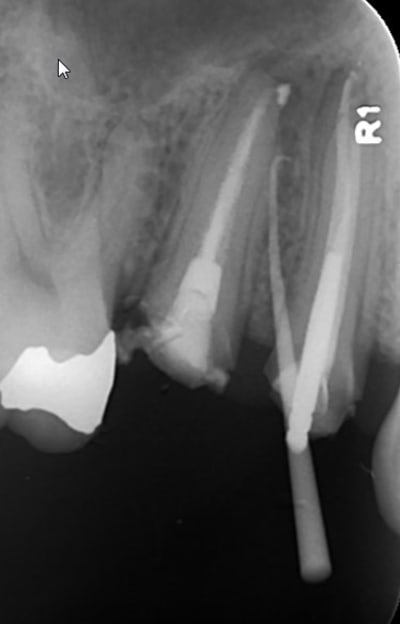

Ci joint un cas vu le 29/04/2014 pour une douleur à la mastication au niveau des prémolaires sup. droites. Douleurs à la percussion au niveau de 14 et 15. Aucune réponse au test thermique au niveau de 14.

Je décide de traiter en 1ère intention la 14 nécrosé. Les symptômes diminuent largement, mais il demeure une zone douloureuse à la palpation au niveau de la table vestibulaire (la lésion est palpable entre les deux racines 14-15).

Le patient pas très sérieux disparait avec sa provisoire durant plus d'un an...

Il refait surface en Août 2015! La lésion est toujours visible à la radio. Le kyste est toujours palpable en vestibulaire. La palpation est toujours douloureuse.

On décide de déposer la couronne et l'ic de la 15, afin de refaire le traitement canalaire des deux dents 14 et 15.

Suite au retraitment de la 15, une fistule apparait en vestibulaire. La radio cône de gutta dans la fistule montre que celui-ci remonte jusqu'à la lésion (peut être plus au niveau de l'apex de la 15?!). Comme le canal V de la 14 n'est pas obturé jusqu'à l'apex je décide de retraiter ce canal...

Patient revu ce matin, la fistule de ne referme toujours pas, et ça gonfle par intermittence selon les dire du patient, mais le cône de gutta ne remonte plus jusqu'au niveau des apex de 14 et 15... (signe de début de guérison?)

Je décide de retraiter la 15, mais cette fois-ci j'obture au MTA + cônes de gutta ; j'ai pas encore de biocéramique... :-(

Un cône beam a été prescrit, et l'étape suivante est la résection apicale si la fistule ne se referme pas la semaie prochaine!